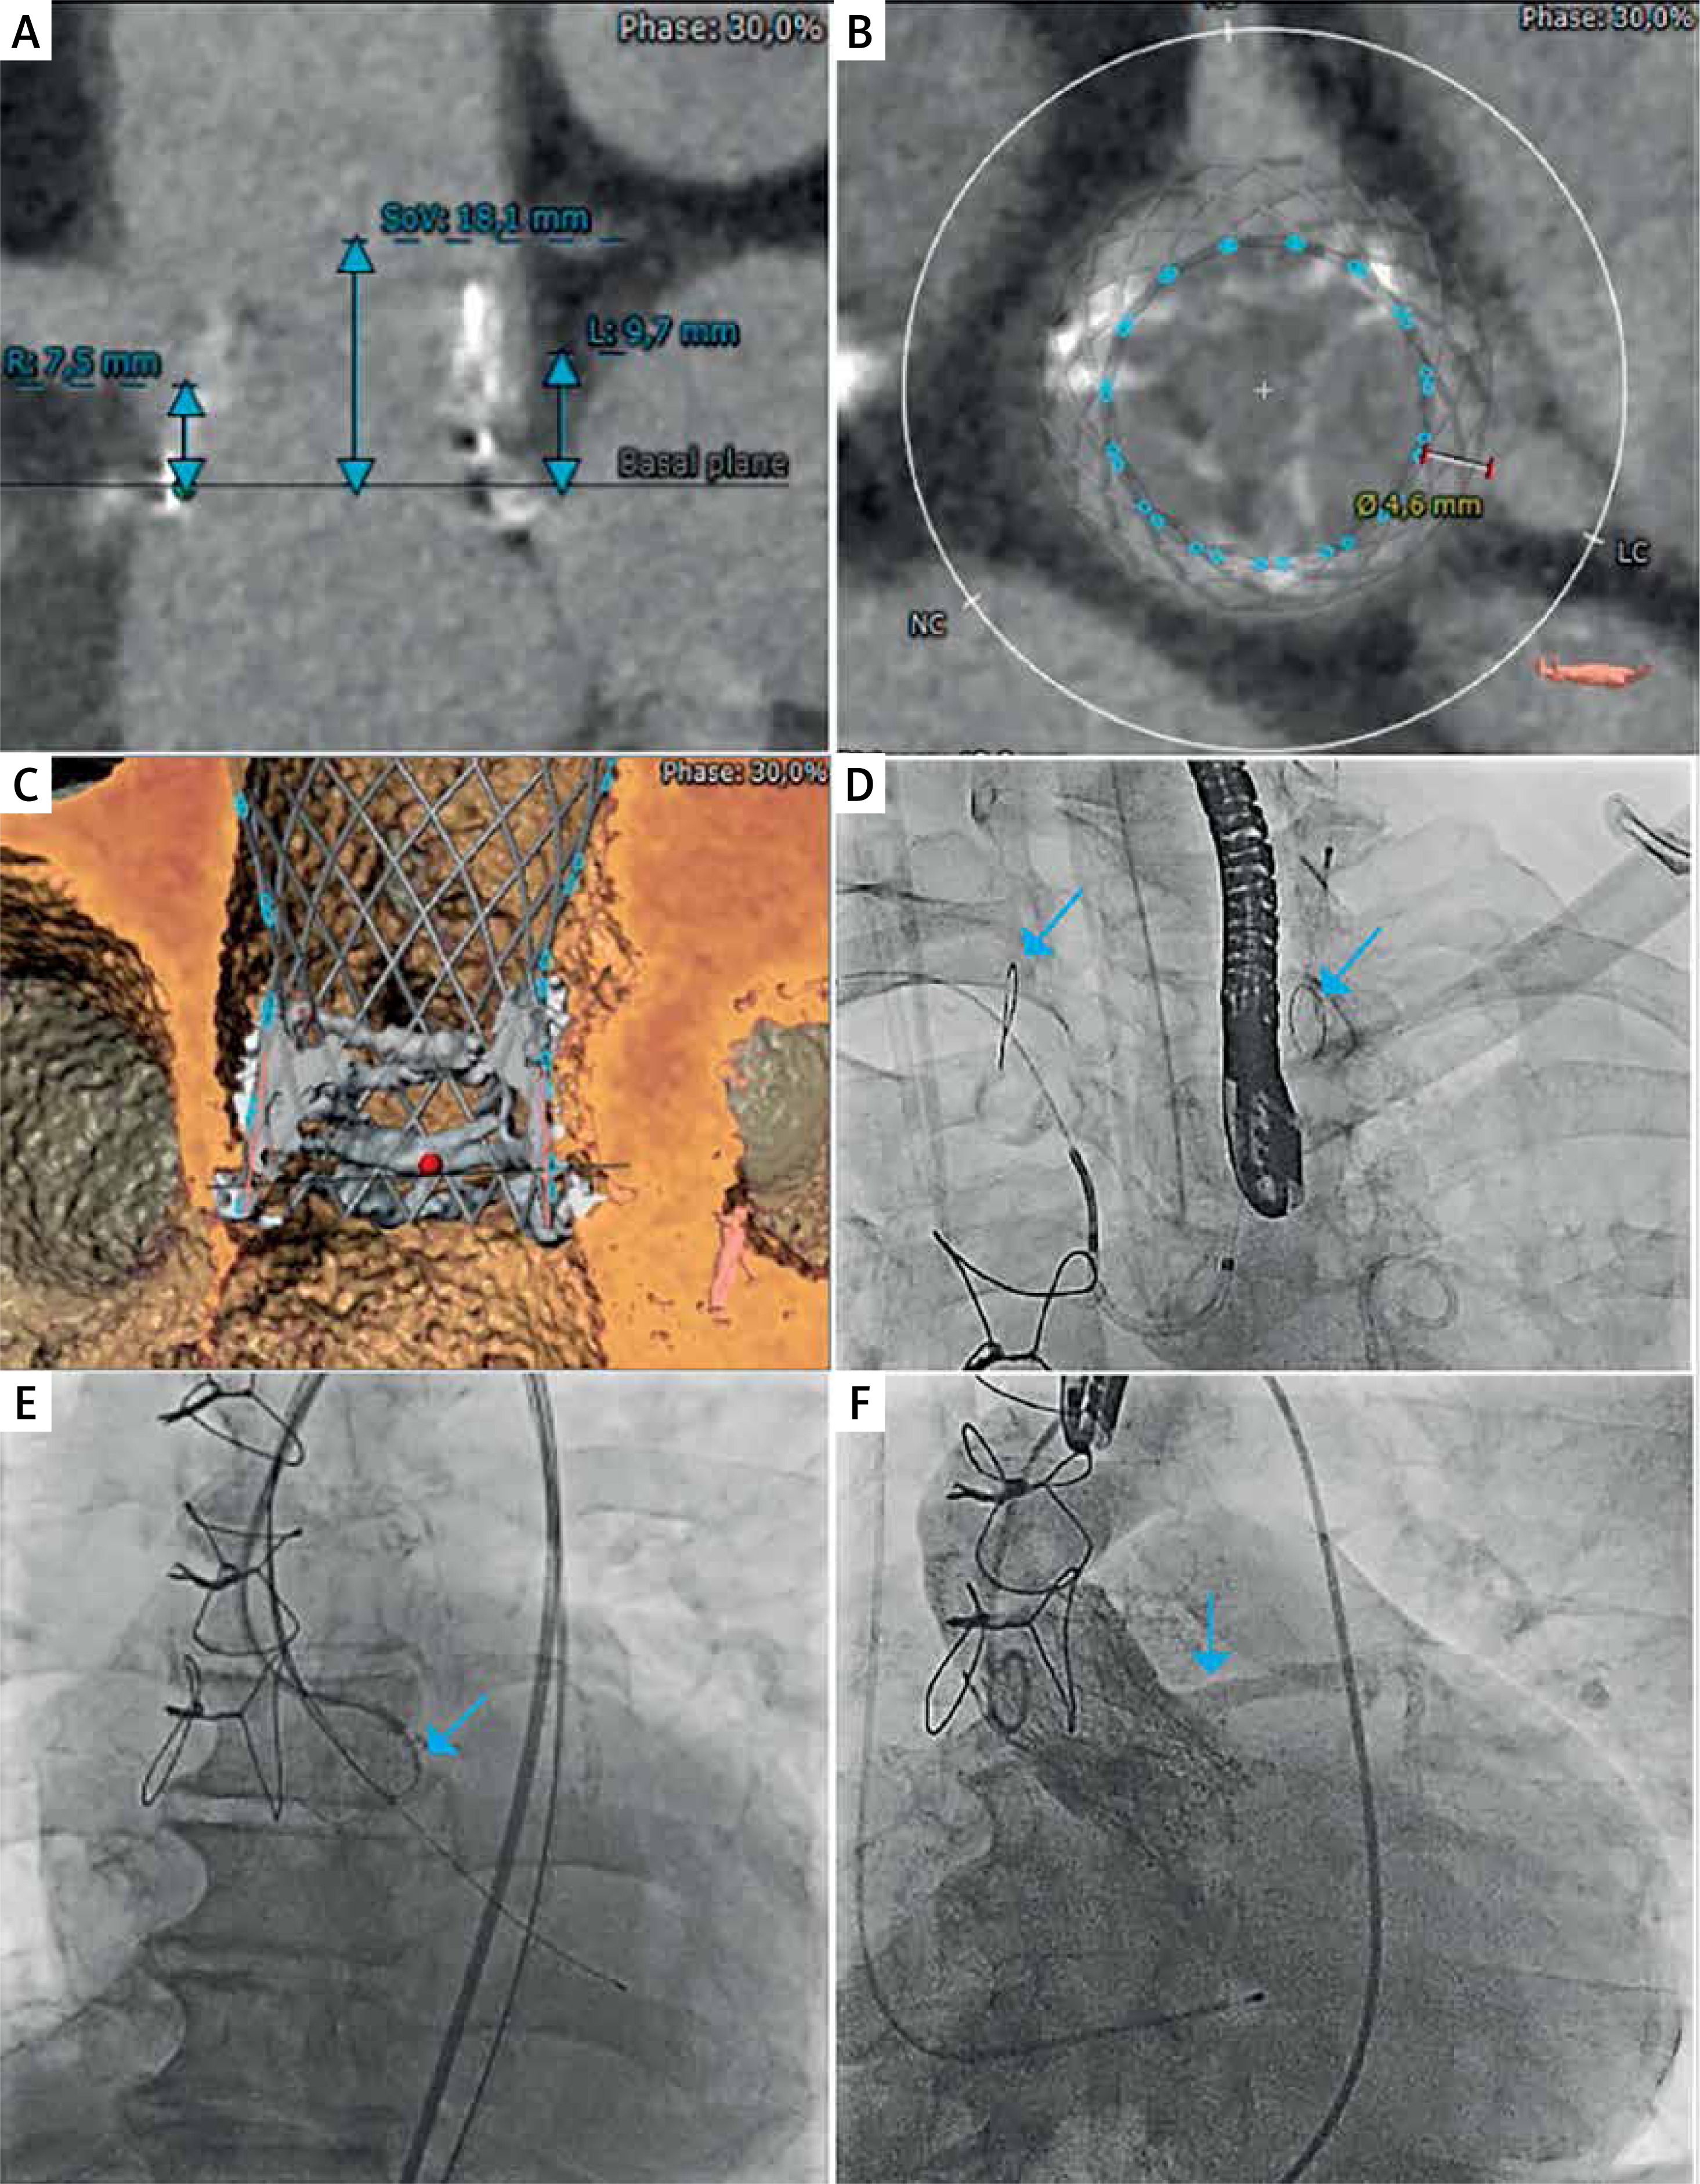

We present a case of a 66-year-old man after the mini-Bentall procedure with severe dysfunction of the aortic bioprosthesis (Trifecta GT 25 mm), admitted to the cardiology department due to exacerbation of chronic heart failure to NYHA class III. His medical history included percutaneous coronary intervention with stent implantation in the left anterior descending artery and intermediate branch, peripheral artery disease and hypercholesterolemia. Transthoracic echocardiography (TTE) revealed global hypokinesis of the left ventricle (ejection fraction, EF 35%), severe stenosis (Vmax 5.6 m/s, max/mean gradient 125/77 mm Hg, indexed aortic valve area 0.24 cm2/m2) and moderate regurgitation of the aortic bioprosthesis. Computed tomography revealed a virtual transcatheter heart valve-coronary (VTC) distance to the left coronary artery of only 4.6 mm (Figures 1 A–C). Considering the high peri-operative risk (EuroSCORE II 13.2%) and high risk of coronary occlusion [5], the patient was qualified for ViV TAVR using BASILICA and SENTINEL CPD (Boston Scientific, US).

Figure 1

A – Aortic valve long axis showing the distance between the bioprosthesis and ostium of the right coronary artery (R), left coronary artery (L) and sinus of Valsalva (SoV). B – Aortic valve short axis with a virtual ring at the level of the coronaries revealing virtual transcatheter heart valve-coronary (VTC) distance to the left coronary artery of only 4.6 mm. C – Three-dimensional reconstruction showing the stent of the surgical bioprosthesis above the left main ostium. Red dot: hinge point of the bioprosthetic leaflet at left coronary cusp. Green dot: hinge point of the bioprosthetic leaflet at right coronary cusp. D – Deployment of the SENTINEL cerebral protection device – filters in the brachiocephalic trunk and left common carotid artery are indicated with blue arrows. E – Laceration of the left coronary cusp using the BASILICA technique – electrocautery wire is indicated with a blue arrow. F – Patent left coronary artery after valve-in-valve Evolut R 26 mm bioprosthesis implantation (blue arrow)

The SENTINEL was delivered via the right radial artery (6-Fr sheath) and the filters were deployed in the brachiocephalic trunk and the left common carotid artery (Figure 1 D). TAVR and BASILICA were performed via the right and left femoral accesses (14-Fr and 7-Fr sheath) under transesophageal echocardiography (TOE) guidance. For BASILICA, multipurpose and Amplatz left 2.0 catheters were inserted through the femoral arteries and placed either side of the aortic valve. A vascular snare and an electrified cutting wire were inserted into the left ventricular outflow tract to create an electric cutting knife below the left coronary leaflet (30 W). Next, the leaflet was lacerated (70 W), ensuring its splay around the left coronary ostium (Figure 1 E), and the Evolut R 26 mm bioprosthesis was implanted with no blood flow obstruction in the coronary arteries (Figure 1 F). Aortography and TOE showed no evidence of paravalvular leakage. The SENTINEL was removed at the end of the procedure. Small embolic debris (0.5–1 mm) were found in the filters. The femoral artery was closed using the ProGlide system. There were no conduction problems after the procedure.